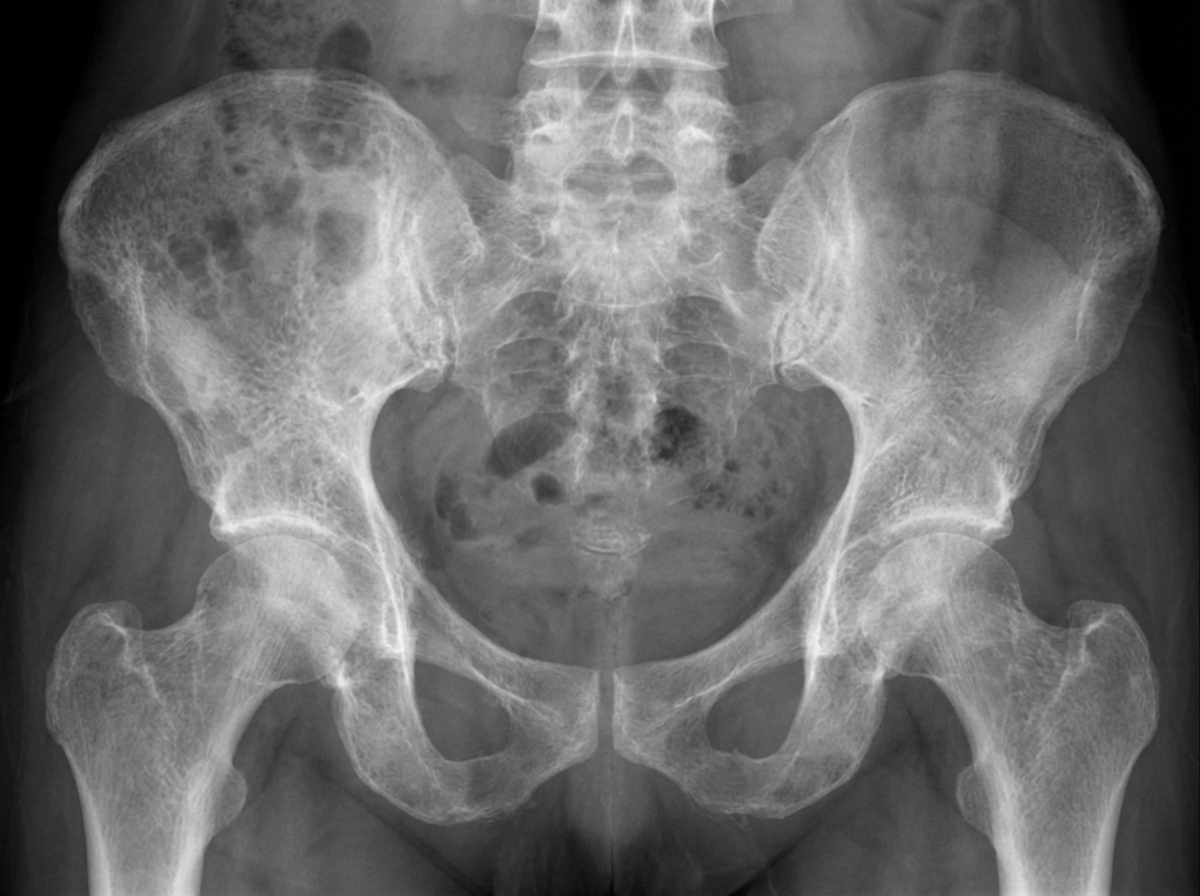

X-Ray (Wrist AP view is best):

- Metaphyseal changes: Cupping, Fraying, Splaying

- Widening of the epiphyseal plate

- Generalized osteopenia & cortical thinning

- Looser's zones: Pseudofractures

- Wrist & knee X-rays show metaphyseal cupping, fraying, and splaying.